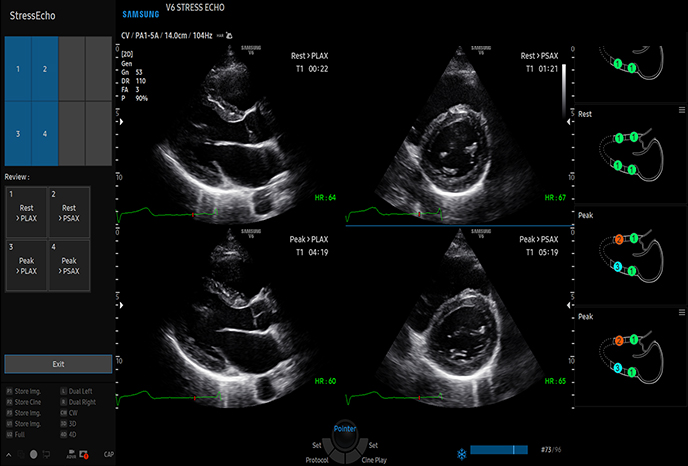

스트레스 에코

심장심장의 해부학 구조 및 혈류역학적 평가, 순환기계 장애, 심장 수축·이완

고급 실시간 3D(4D)로 시각화 가능